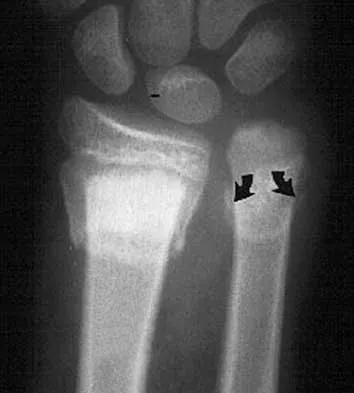

What muscle attaches to the site shown by the arrow in Figure 2?

Explanation

The latissimus dorsi inserts on the humerus metaphysis between the pectoralis major (posterior) and teres major (anterior). Teres minor inserts on the base of the greater tuberosity. Pectoralis minor does not insert on the humerus. Williams PL, Warwick R, Dyson M, Bannister LH: Neurology, in Gray's Anatomy, ed 37. Edinburgh, Scotland, Churchill Livingstone, 1989, pp 1131-1132.